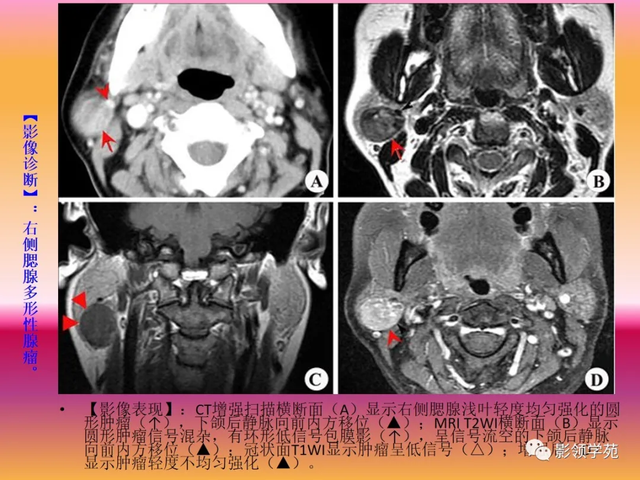

多形性腺瘤(混淆瘤)

多形性腺癌(pleomrphicadenom)是一种包膜情形 纷歧,光镜下以结构多形性而不是细胞多形性为特征的肿瘤。通常上皮和变异肌上皮因素 与黏液、黏液样组织或软骨样组织混淆存在。曾以为 黏液软骨样组织来自间叶组织,故又称为混淆瘤(mixedtumor)。

多形性腺瘤是最常见的涎腺肿瘤,凭证 统计,多形性腺瘤占涎腺上皮性肿瘤的51%,占其良性肿瘤的88%。可发生于任何年岁 ,以30~60岁最多见,平均就诊年岁 是46岁。女性略多于男性。

约80%发生于腮腺,其次为下腺下腺,舌下腺有数 。